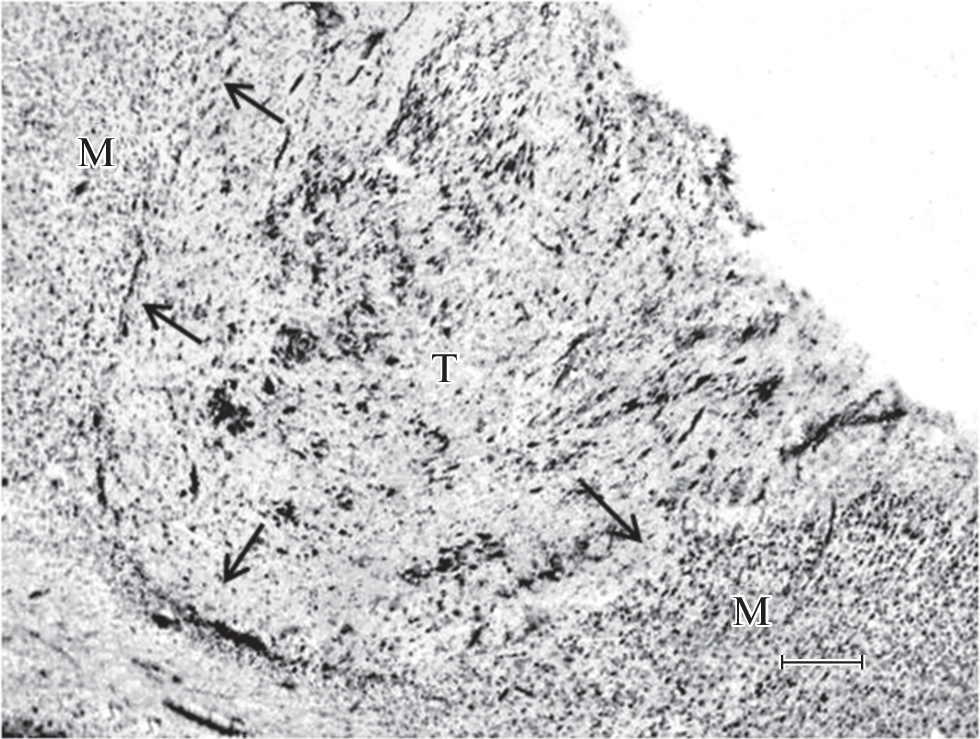

Гамма-аминомасляная кислота (ГАМК) играет важную роль в регуляции развития и функционирования мозга. Целью работы было исследование участия ГАМК, содержащейся в ненейрональных клетках, в дифференцировке и созревании неокортикальных трансплантатов крыс. Трансплантировали кусочки фетального соматосенсорного неокортекса в острую полость гомотопической области коры взрослых крыс-самцов. Через 4 мес. после операции проводили гистологическое и электронно-микроскопическое изучение трансплантатов. Трансплантаты были хорошо васкуляризованы и состояли из нейрональных и глиальных клеток. Локализацию ГАМК в ненейрональных клетках исследовали с помощью ультраструктурной иммуноцитохимии с использованием антител, конъюгированных с коллоидным золотом. Наибольшая экспрессия иммунометки в виде электронно-плотных глобул размером от 20 до 60–80 нм была обнаружена в протоплазматических астроцитах и их отростках. Астроцитарные концевые ножки вокруг капилляров также содержали ГАМК-позитивные гранулы. Кроме того, ГАМК-положительные гранулы наблюдались в некоторых миелинобразующих клетках и в эндотелиальной стенке кровеносных сосудов. Полученные результаты показали, что в неокортикальных нейротрансплантатах ГАМК-ергическая сигнализация посредством ненейрональных клеток участвует в морфофункциональной дифференцировке трансплантированной ткани.